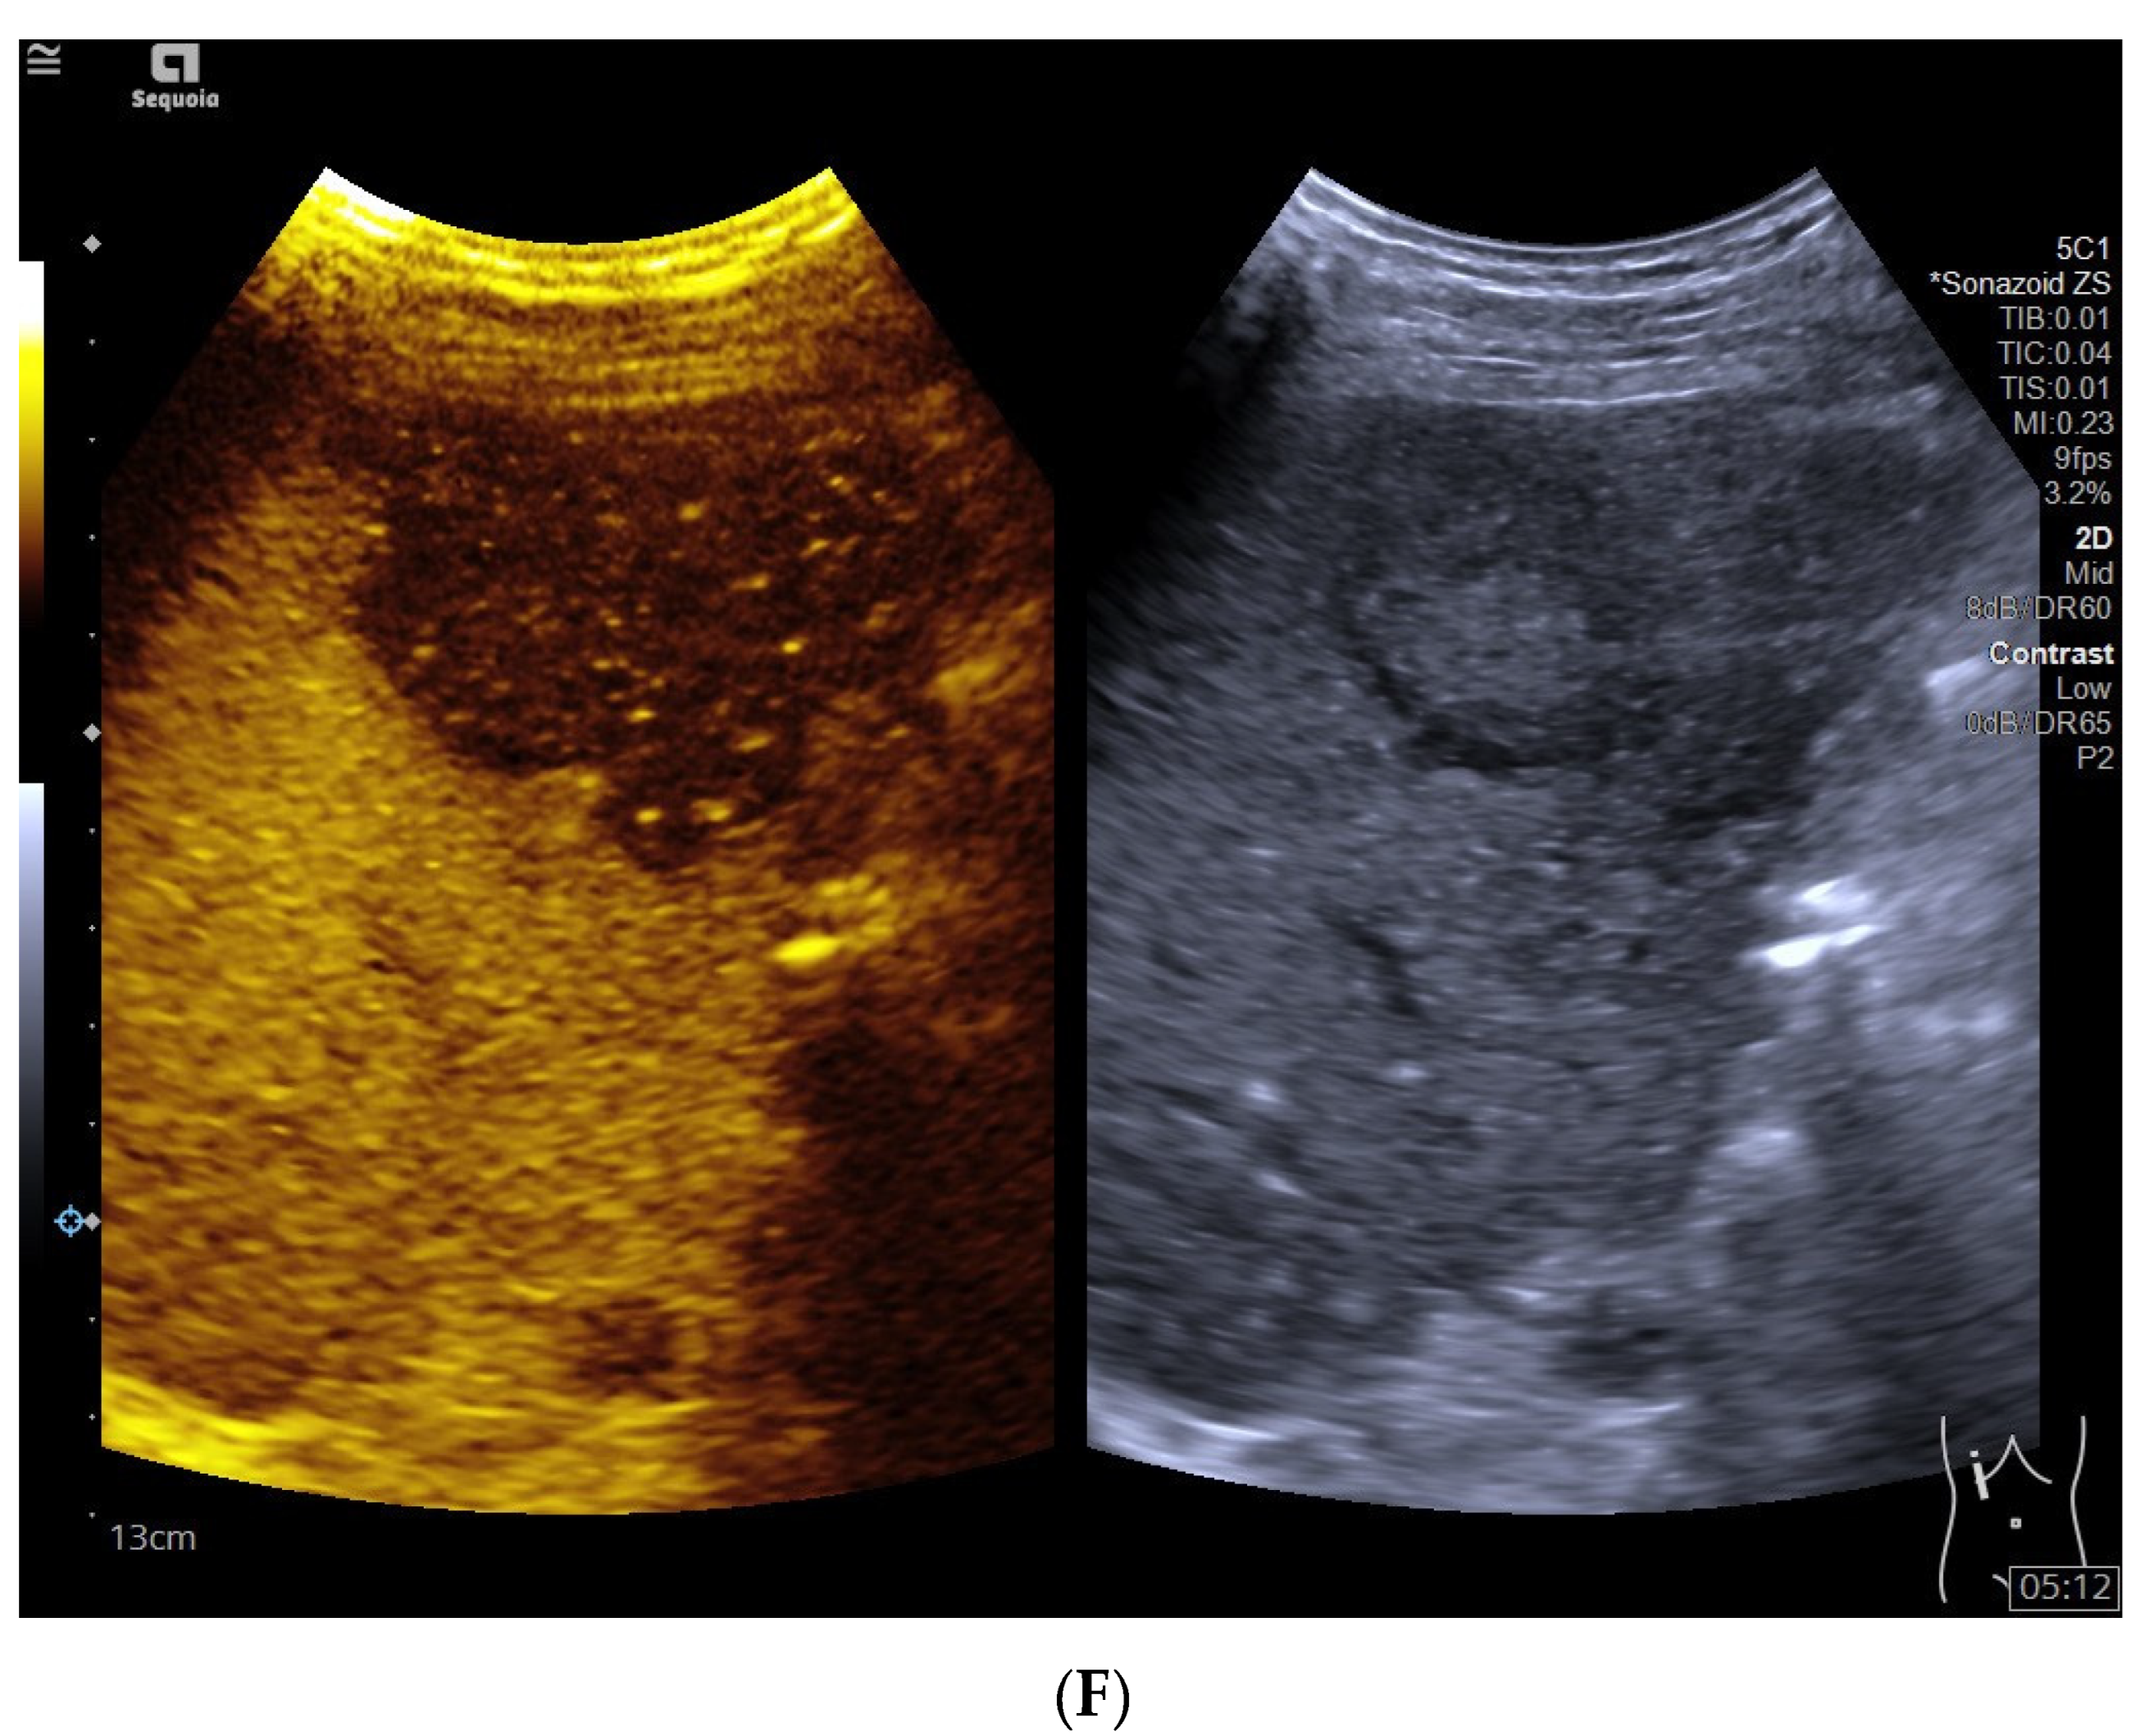

3.4. CEUS Features

3.5. Time Begin to Washout

| Late phase | 0.226 | ||

| Isoenhancement | 0 | 5 (13.9%) | |

| Hypoenhancement | 19 (100%) | 31 (86.1%) | |

| Kupffer phase | / | ||

| Hypoenhancement | 19 (100%) | 36 (100%) |